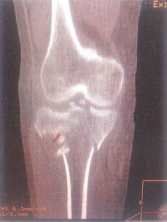

Phim chụp cắt lớp vi tính mâm chày với 3 bình diện: ngang (horizontal), trán (coronal), đứng dọc (sagittal) thể hiện toàn cảnh, chi tiết tổn thương, đặc biệt tổn thương diện khớp, rất hữu ích cho kế hoạch phẫu thuật.

Hình 11.5. Hình ảnh cắt lớp vi tính gãy mâm chày [Handbook of Fractures, 5E (2014).]